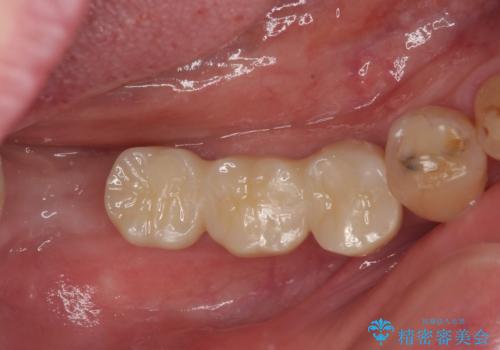

伸び出してきた上顎奥歯 部分矯正を用いた奥歯の補綴治療